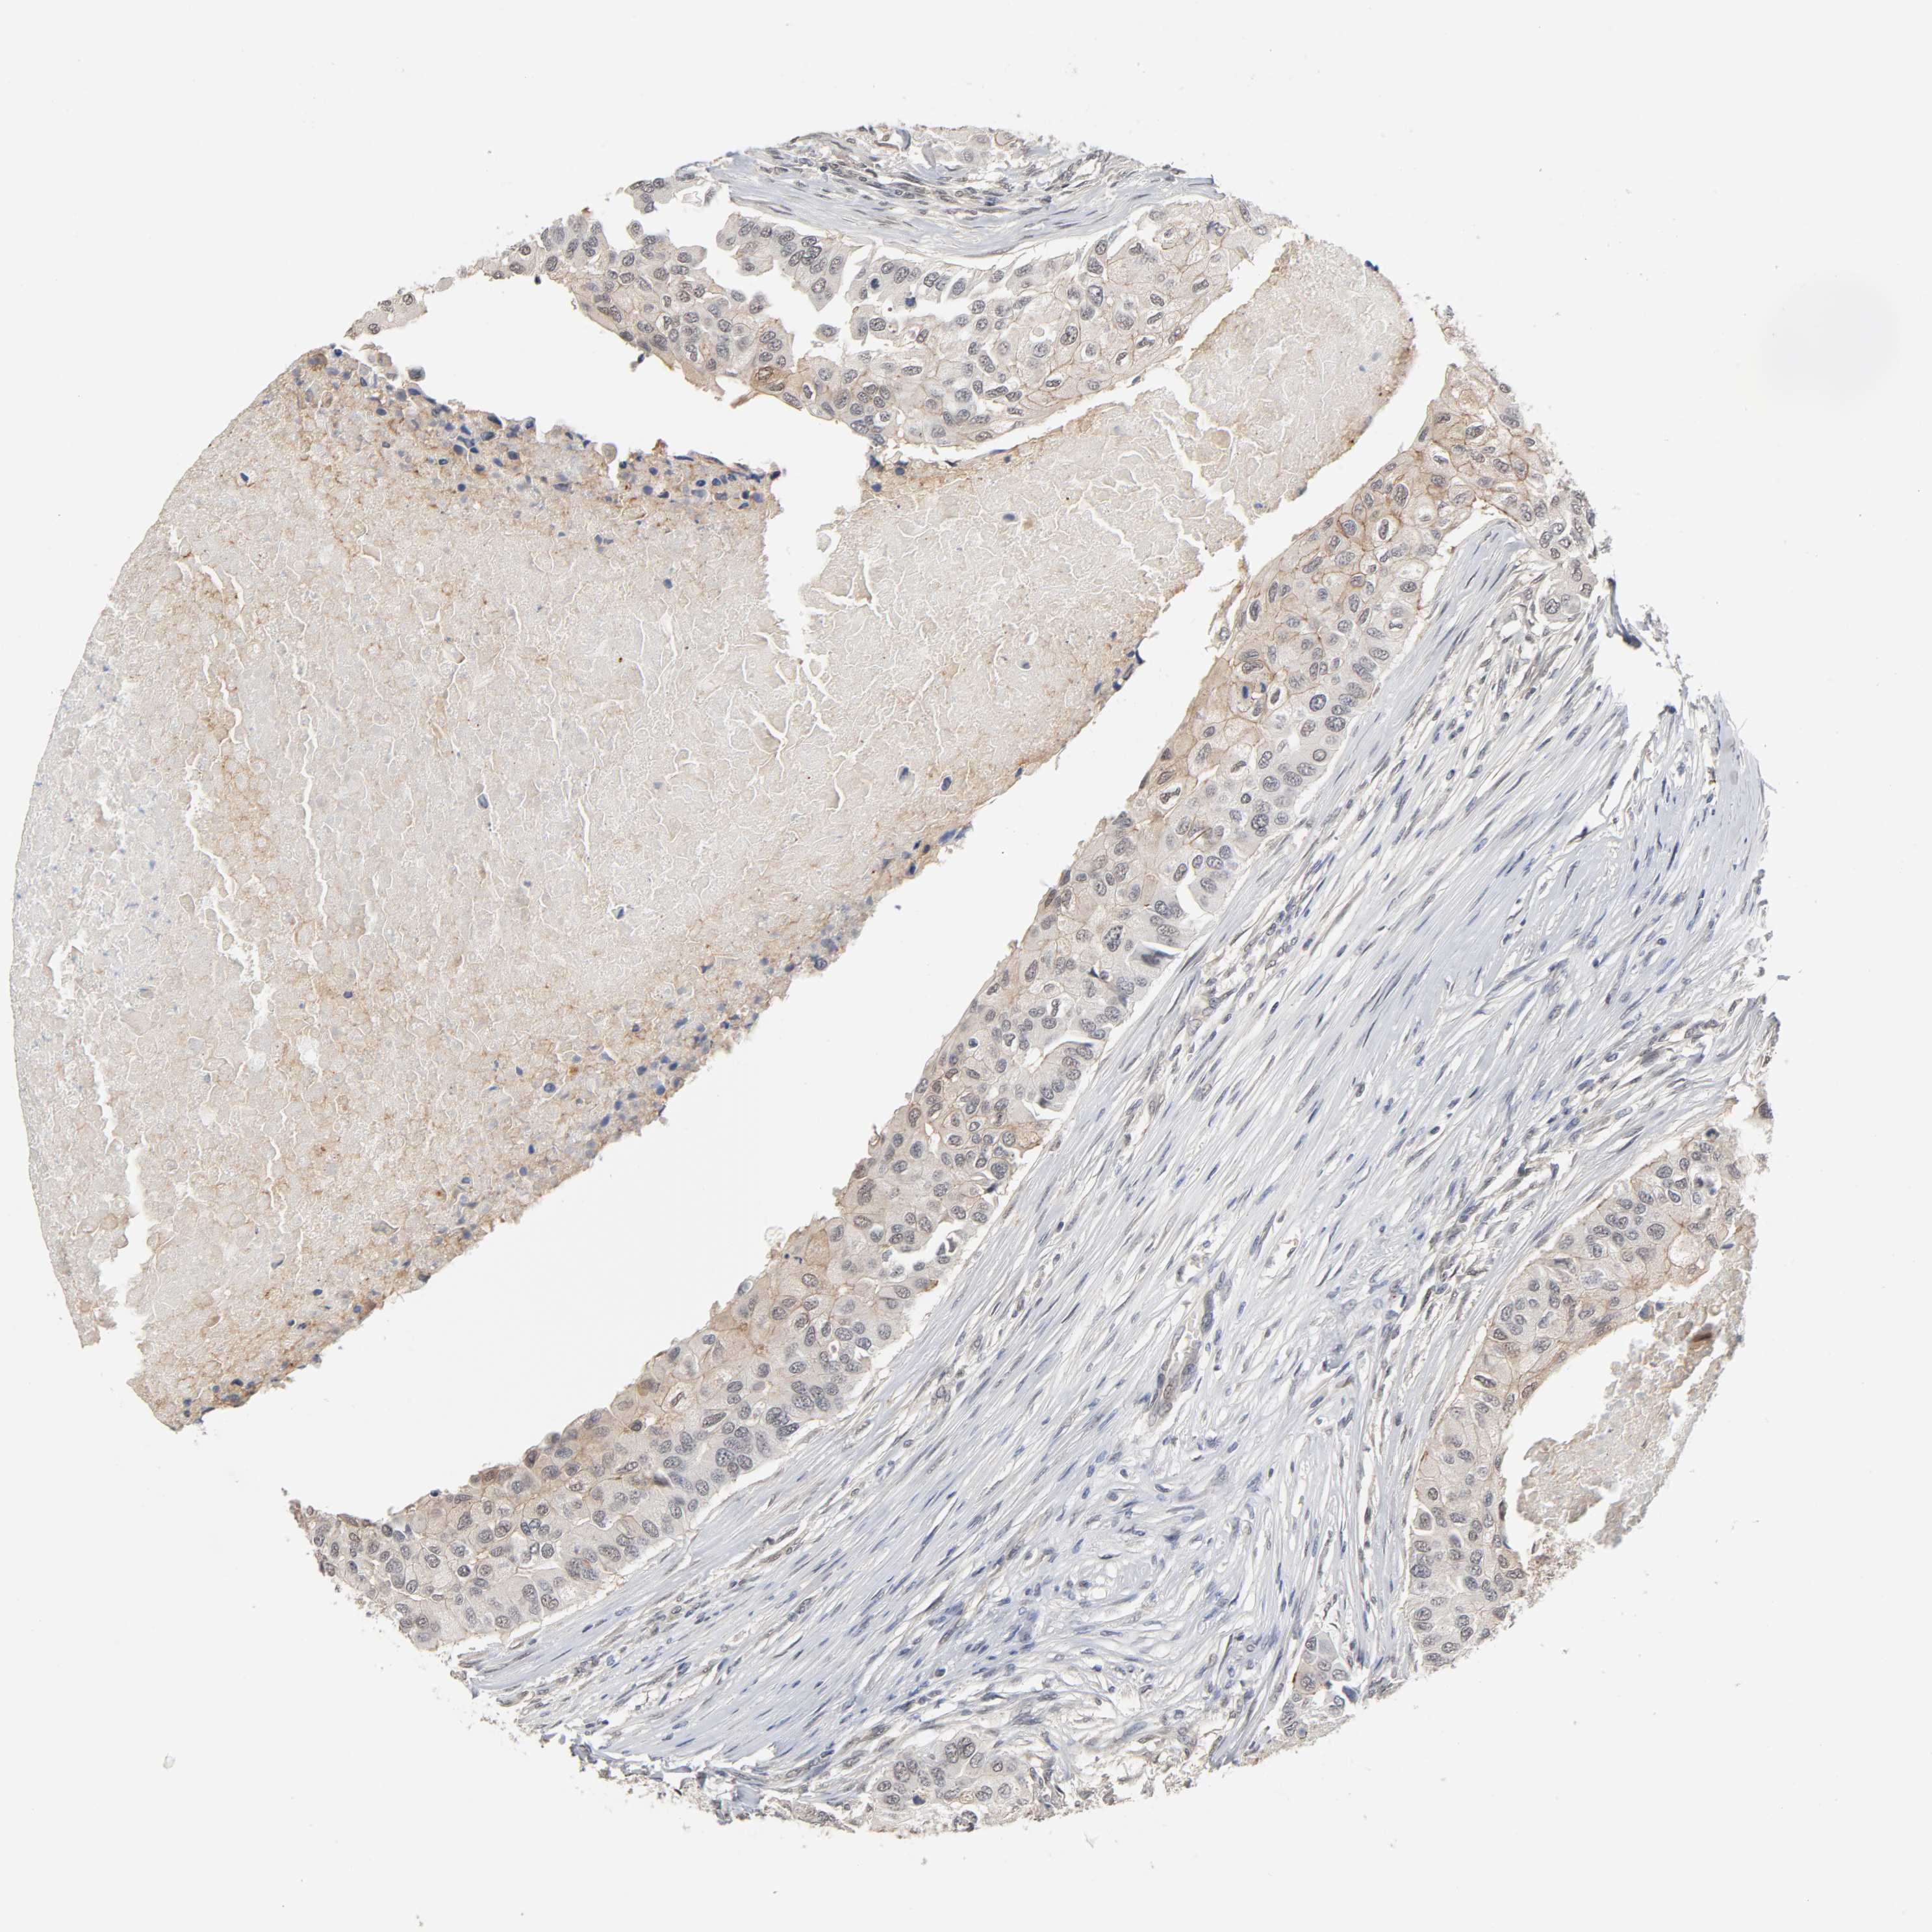

BRCA TCGA BRCA VALIDATION PROTEIN EXPRESSION

ANTIBODIES

AND

VALIDATION